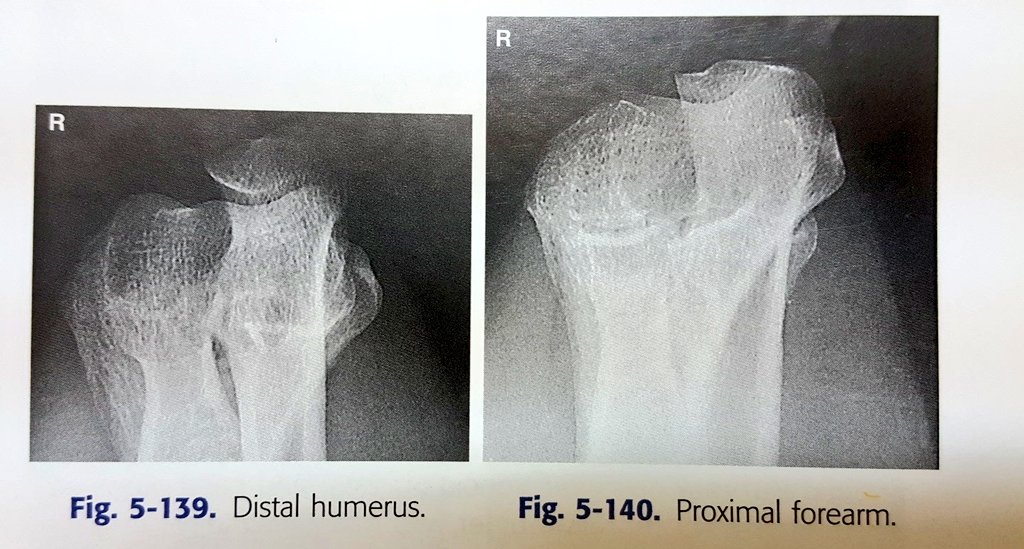

لأن كل زاوية ستظهر تشريح محدد(في الصورة)

١.الزاوية الأولى عمودية على محور humerus

٢.الزاوية الثانية عمودية على forearm.